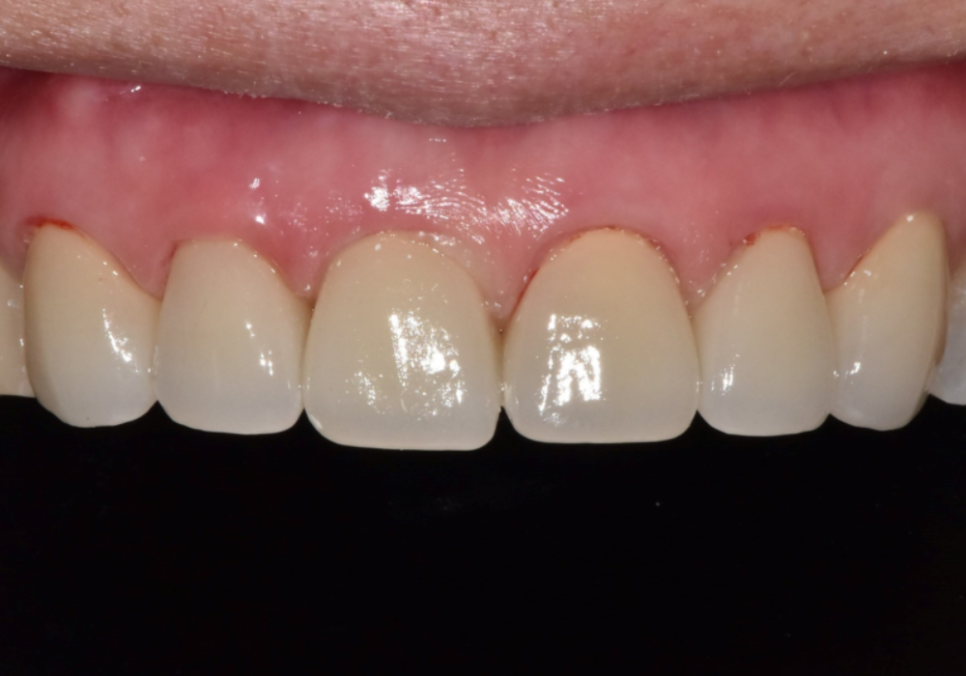

금이 간 앞니 6개,

싱글 크라운으로 진행한 환자 사례

얼마 전 저희 치과를 방문하신 환자분은

앞니 6개(#13~23)가 씹는 힘을

견디지 못해 가운데에

금이 가 있는 상태였습니다.

치아는 마모되어 짧아져 있었고,

씹는 면 쪽은 상아질이 드러나 보일 정도로

마모가 진행되어 있었죠.

240201(전) 240221(후)

싱글 크라운을 선택한 결과

고덕동 앞니 보철, 브릿지와 싱글 크라운, 어떤 선택이 나에게 더 유리할까?